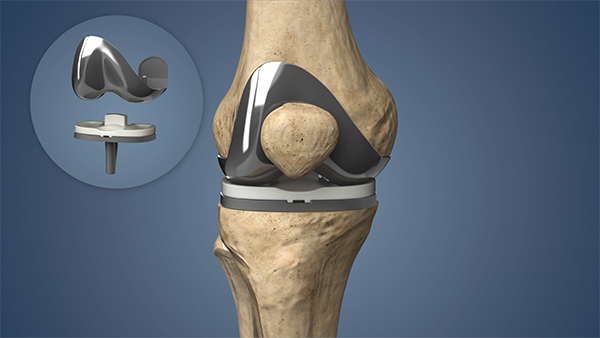

Knee replacement surgery, or knee arthroplasty, has become a routine solution for individuals suffering from chronic arthritis or severe knee injuries. The procedure replaces the damaged joint with metal and plastic components to restore mobility and relieve pain. However, true recovery begins after the surgery. This article will walk you through what to expect post-surgery, how to move safely, and how to support a strong, lasting recovery.